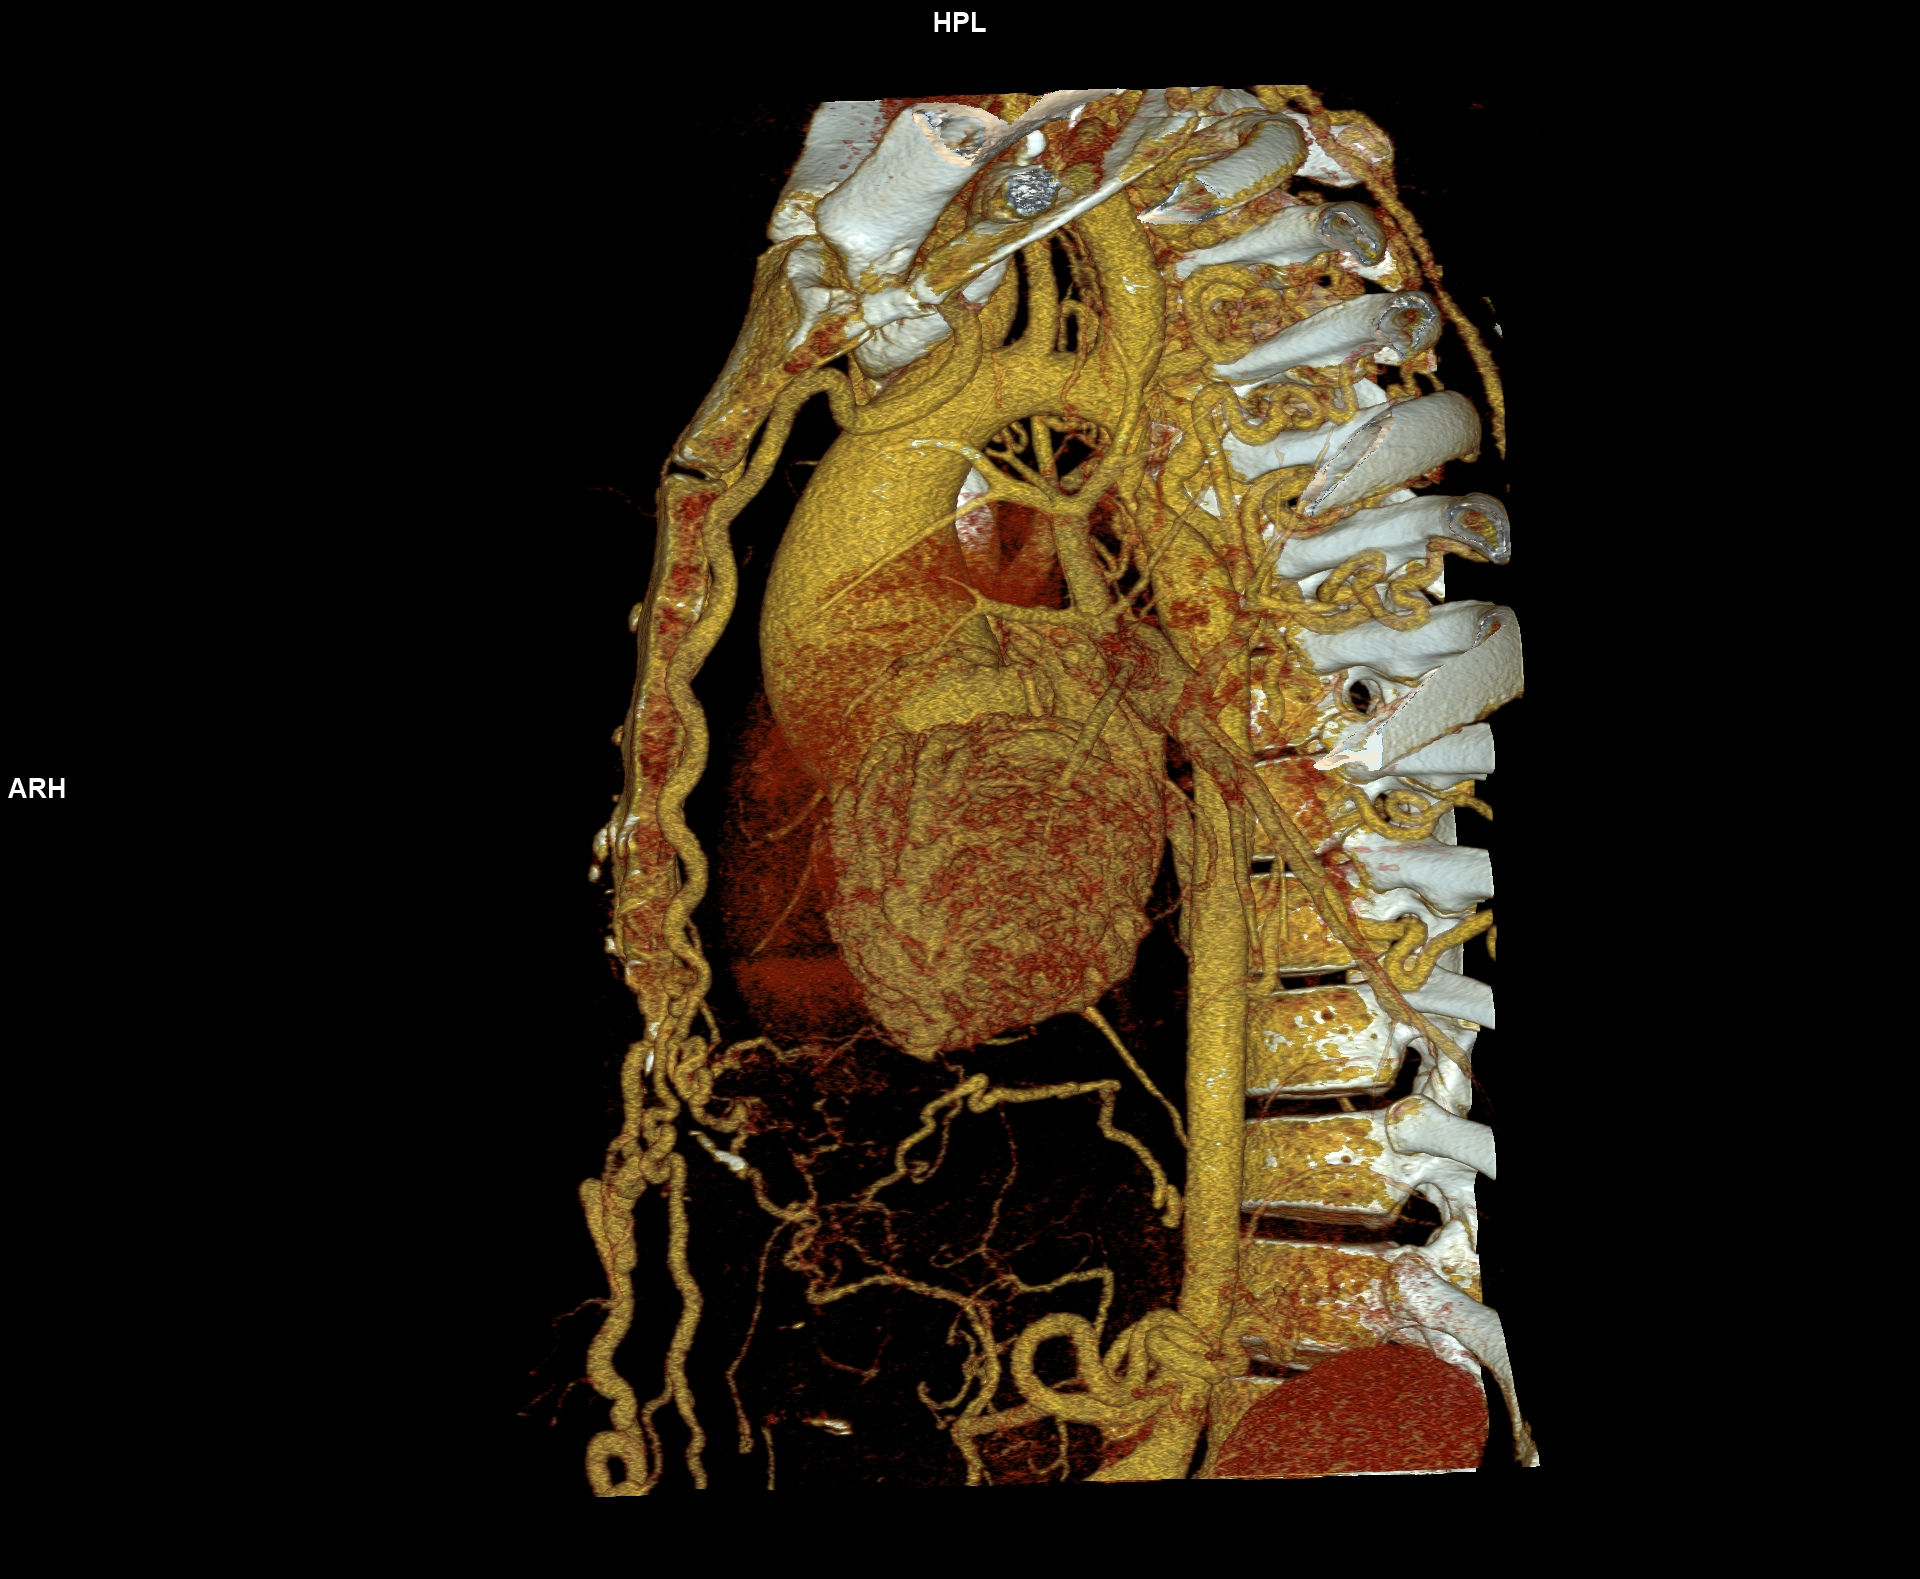

Figurile 6-10: reconstrucții volumice (VRT) din achiziție angioCT aorta toracică

Discuţie caz nr 109: Pacient cu suspiciune de coarctaţie de aortă – are indicație de angioCT aortă toracică; medicul radiolog la acești pacienți este indicat să efectueze investigația cu sincronizare ECG deoarece coarctaţia de aortă poate fi asociată și cu bicuspidie de valvă aortică, mai ales că la acest pacient ecografia cardiacă descria creștere de calibru a aortei ascendențe. Pe reconstrucția cine în planul valvei aortice din achiziția cardioCT cu sincronizare ECG se remarcă o valvă aortică morfologic tricuspidă, funcțional bicuspidă ce asociază ectazie de aortă ascendentă și coarctaţie de aortă descendentă cvasicompletă cu dezvoltare de circulație colaterală intercostală și mamară internă.